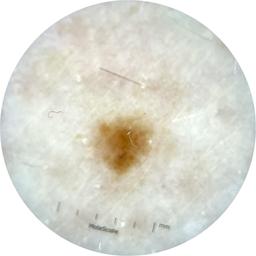

ISIC_9785574

Information

2003 x 2003

Attribute to

MEL-SELF Trial, https://www.sydney.edu.au/medicine-health/our-research/research-centres/melself-project.html

Field Value

acquisition_day 148

age_approx 45

anatom_site_1 Head and neck

anatom_site_general head/neck

concomitant_biopsy False

diagnosis_1 Benign

diagnosis_confirm_type single image expert consensus

family_hx_mm True

image_manipulation instrument only

image_type dermoscopic

lesion_id IL_0236417

patient_id IP_8456088

personal_hx_mm True

sex female